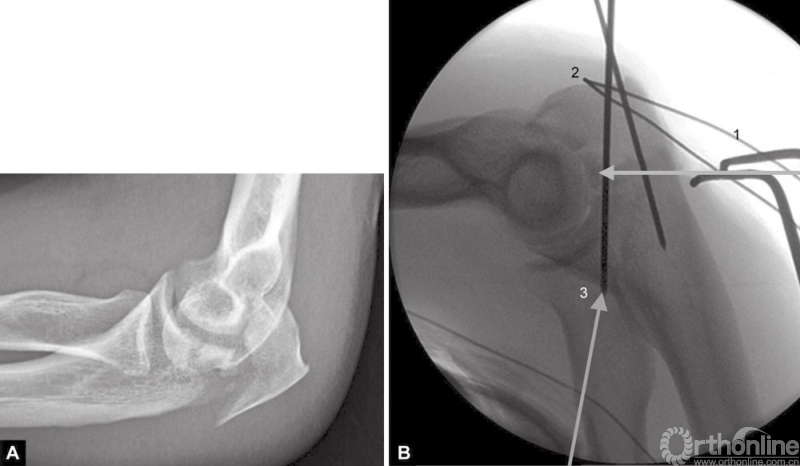

当存在鹰嘴关节面部分压缩时,必须将其对应肱骨滑车抬高复位。在三头肌止点用钢丝牵开鹰嘴尖端(图4),复位压缩骨折,用细克氏针将其推靠在肱骨滑车上维持位置。克氏针必须紧贴压缩骨折部位的软骨下骨来维持位置。此时,用高质量的侧位X线片检查来确定压缩骨折的复位,克氏针的位置是否良好是非常必要的。另一种方法是采用松质骨植骨来支撑复位的压缩骨折。

图4A和B(1)将鹰嘴拉下复位关节内松动的骨片,用横向箭头所示细克氏针,将其推挤在滑车上维持复位;(2)钢丝环穿过三头肌止点周围将鹰嘴拉下;(3)克氏针紧贴软骨下骨插入支撑松动的关节内骨片(给向箭头所示克氏针)